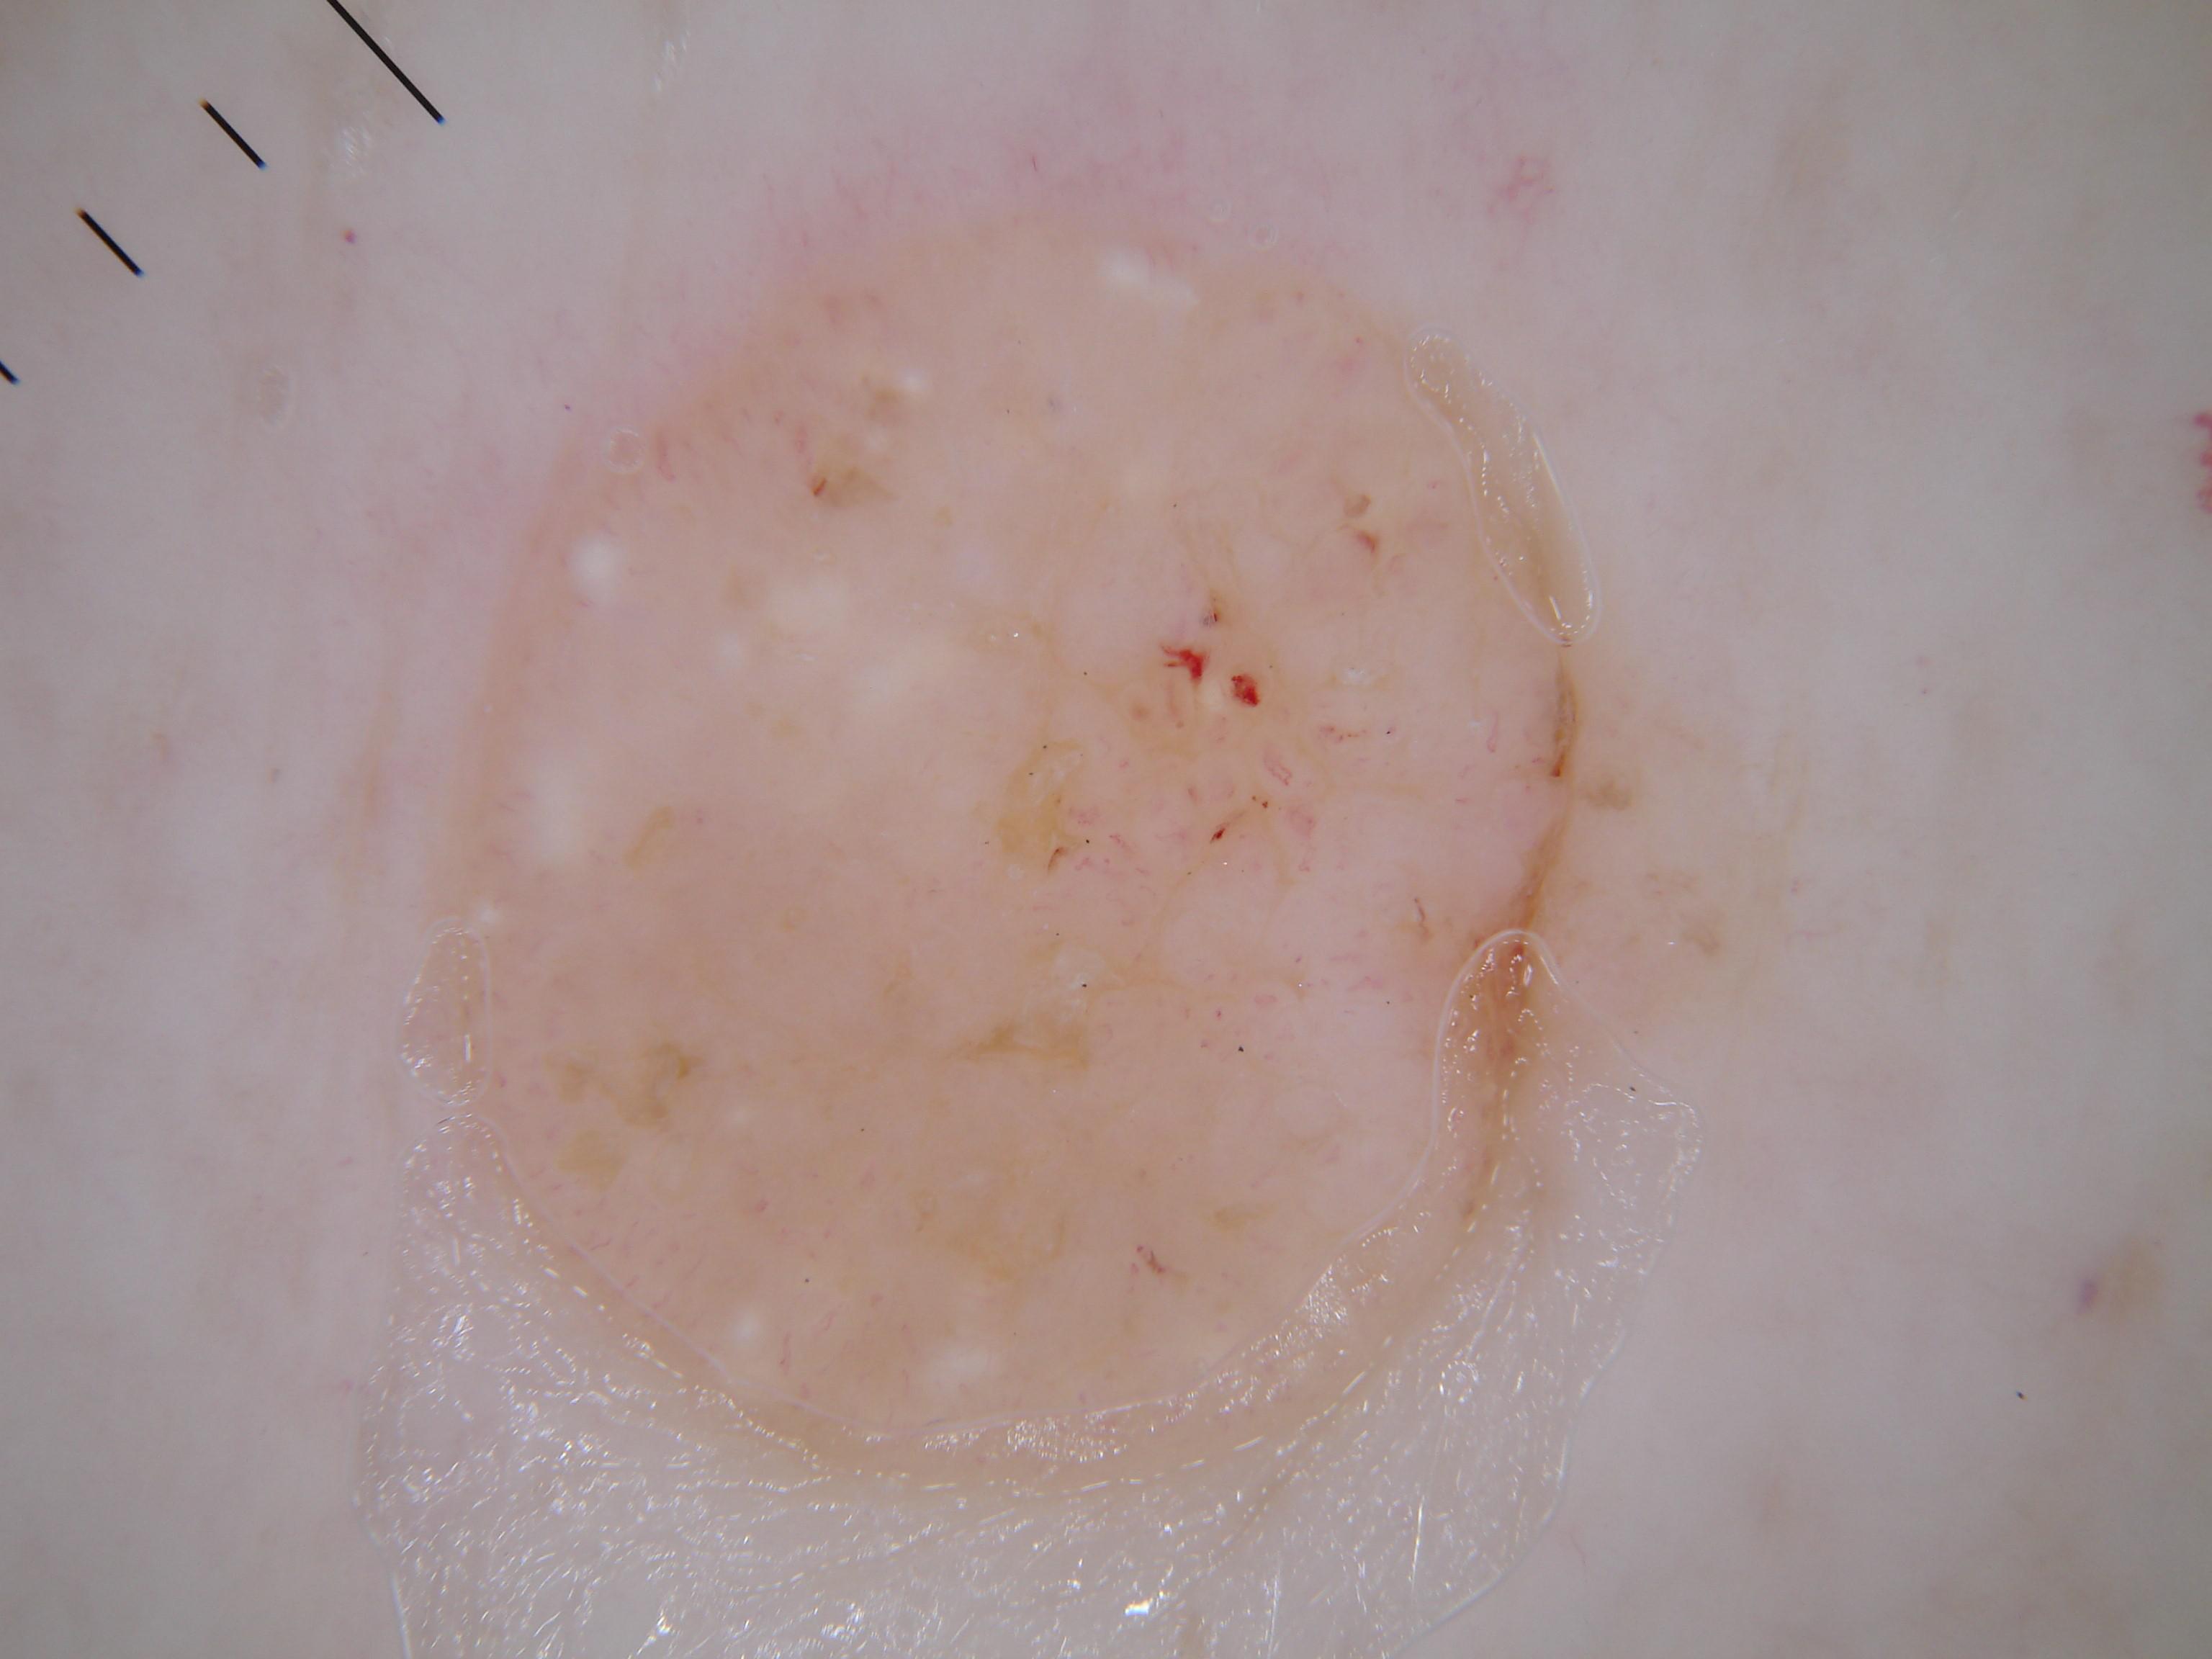

{

"age_approx": 55,

"anatom_site_general": "lower extremity",

"concomitant_biopsy": true,

"dermoscopic_type": "contact non-polarized",

"diagnosis_1": "Benign",

"diagnosis_2": "Benign soft tissue proliferations - Fibro-histiocytic",

"diagnosis_3": "Fibroepithelial polyp",

"diagnosis_confirm_type": "histopathology",

"family_hx_mm": false,

"image_type": "dermoscopic",

"melanocytic": false,

"patient_id": "IP_9132437",

"personal_hx_mm": false,

"sex": "female"

}

"dermoscopic_type": "contact polarized",

"dermoscopic_type": "non-contact polarized",